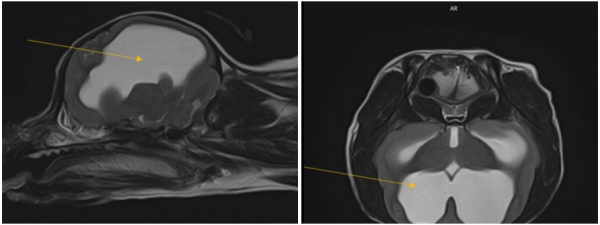

MRI/CT 정밀 영상검사 결과

환축추 아탈구 AAI, 뇌기형 및 수두증

① 환축추 아탈구 (Atlantoaxial Instability, AAI)

- 제1경추(atlas) 와 제2경추(atlas) 사이의 간격이 넓어짐

- 치아돌기(dens) 변위로 인한 척수 압박 유발

- 횡인대와 익인대가 비정상적이거나 관찰되지 않아, 선천적 인대형성 이상 또는 파열 의심

- 척수 내 presyrinx(부종) 및 syringomyelia(척수 공동증) 소견이 나타남

- 이외에도 C2 부위의 dural band와 일부 경추 디스크 퇴행성 변화가 확인됨

② 뇌 기형 및 수두증

- 후두골 기형(Occipital malformation) 으로 인해 소뇌 압박

- 연수의 구부러짐 (medullary kinking) 및 CSF 흐름 장애 발생

- 제1경추의 후방 구조가 두개골과 겹치는 atlanto-occipital overlapping(AOO) 소견도 동반되어,

- 추가적인 뇌압박이 유발

- 뇌실 확장(ventriculomegaly) 및 선천성 수두증(hydrocephalus) 확인

- 다수의 두개골 결손(calvarial defects) 도 관찰되었으나, 뇌 탈출은 없는 상태